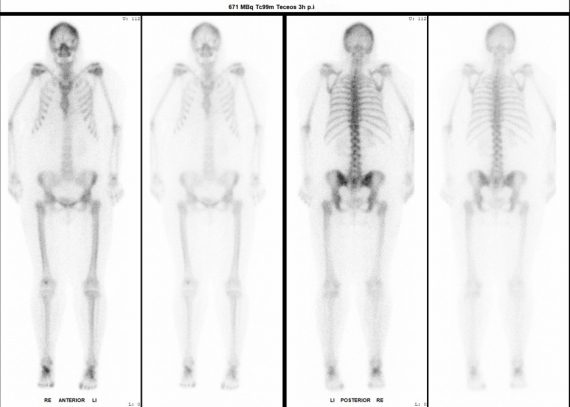

Exemplary case study on skeletal scintigraphy: